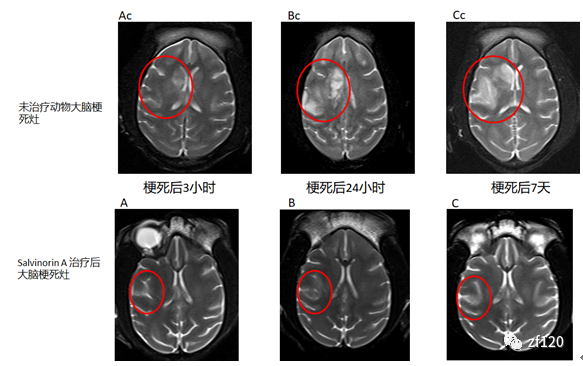

研究结果发现,与对照组相比,salvinorin A显著降低了实验动物的面积/梗死体积(参见图2)。

图2.头颅磁共振成像扫描显示Salvinorin A经鼻腔给药显著减少梗死灶。上图红圈内为为接受治疗动物在梗死后3小时到7天的梗死灶。下图红圈是治疗后大脑的梗死灶。Salvinorin A显著提升了实验动物的神经功能,整体表现为卒中发病7天后就展现出了具有统计学意义的差别,salvinorin A组实验动物的神经功能预后评分(NHPSS评分)优于对照组(见图3)。